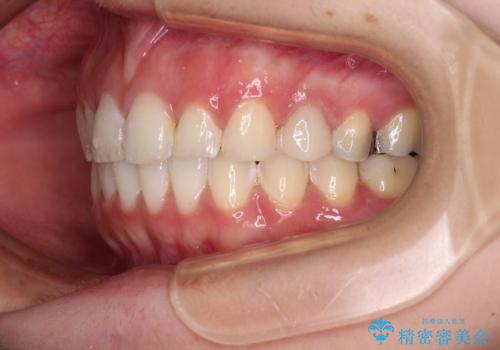

インビザラインでの矯正治療を希望されていましたが、奥歯の咬み合わせがインビザライン単独では改善困難と判断されたので、補助装置を併用することとしました。

まずは裏側の装置やワイヤー矯正を用いて歯列幅の狭い上顎を側方に拡大しつつ全体を後方に移動させ、その後インビザラインにて歯列を整えることとしました。

奥歯の咬み合わせの改善は、インビザライン単独では達成しきれないことがあるため、ワイヤー矯正などの補助装置を併用する場合があります。

インビザライン単独の場合と比べ、治療結果は大きく異なります。